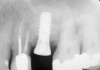

First, a periapical radiograph is taken to determine the amount of bone subantrally. It should be noted that a periapical film has an average error of 14%.23 Therefore, it is advantageous to take the radiograph in a manner that includes a marker (5-mm wide ball bearing) in order to be able to calculate the magnitude of radiographic error (Figure 1).

Figure 1  At tooth site No. 14, a periapical radiograph was taken with the long-cone paralleling technique. The radiographic ball marker measured 5.8 mm while its actual diameter is 5 mm. The enlargement is 0.8 mm, therefore the magnification error is 0.8/5 = 16%. By correcting for this error, a closer approximation of the amount of bone from the osseous crest to the sinus floor can be made.

Figure 1